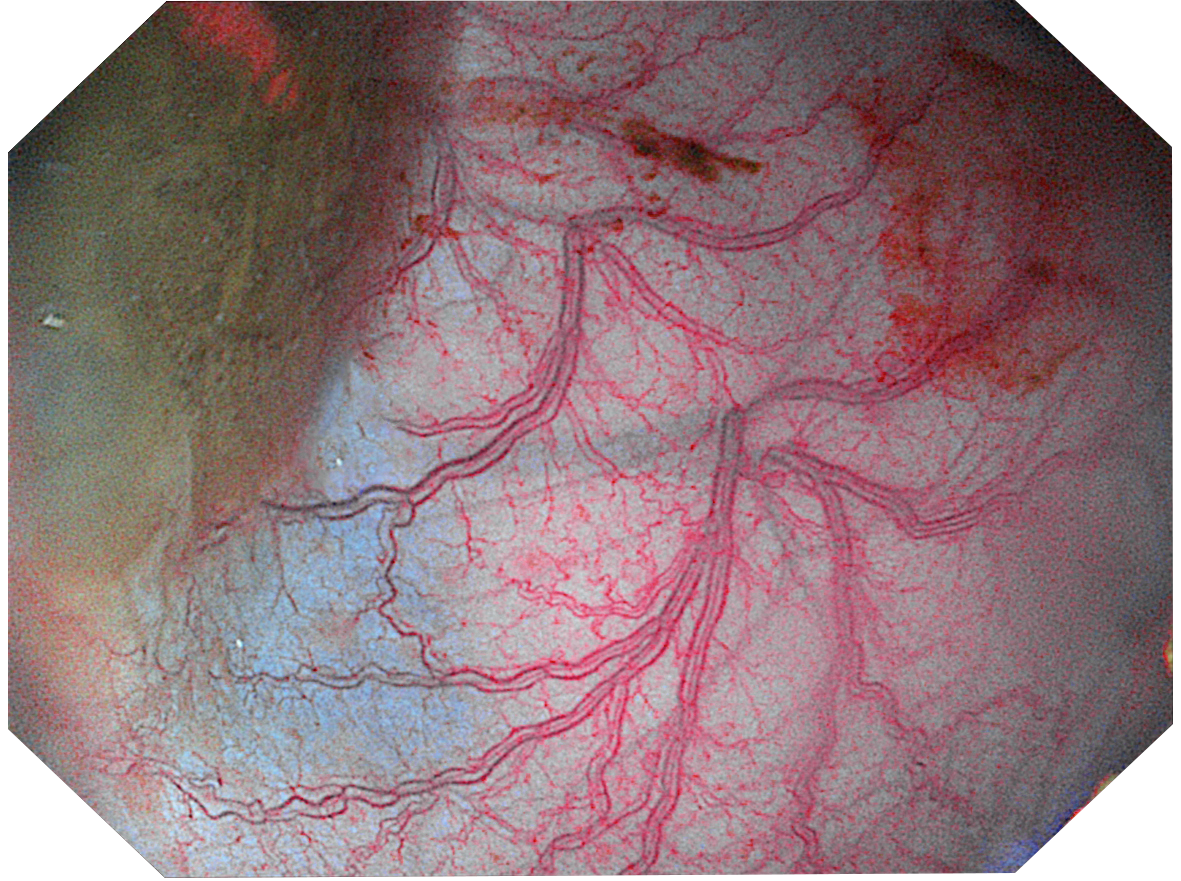

Три режима оптической хромоэндоскопии

Оснащен 4 светодиодными источниками света высокой яркости с независимым управлением, обеспечивающими многоспектральный режим окрашивания «белый свет + 3 спектра CBI». Спектральное окрашивание может повысить визуальный контраст между нормальной тканью и повреждениями, тем самым улучшая выявляемость небольших повреждений. Технология оптического окрашивания (CBI) – удобный и эффективный инструмент для выявления раннего рака, опухолевых и воспалительных процессов.

CBI indigo Усиливает контраст между слизистой оболочкой и кровеносными сосудами. |  |

- CBI indigo — усиление контраста между слизистой и сосудистой сетью.